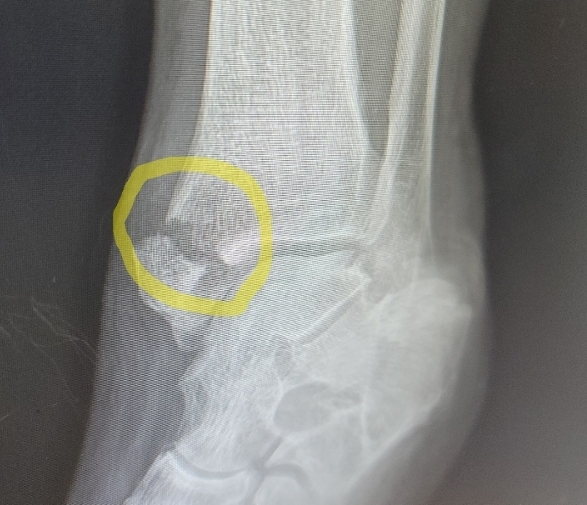

아버지 입원하시다. 2024-09-28(토)

<2024-09-26(목)> 아버지께 전화드리니, "어제 사다리에서 내려오다 발목을 삐어서, 옥산 의원...